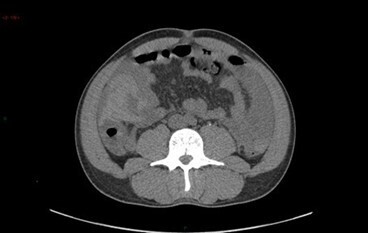

L’analyse des coupes abdominales montre également les images suivantes :

Question 5 - L’aspect évoque (une ou plusieurs réponses exactes) :

Formation transparenchymateuse rénale de densité liquidienne pure au temps portal, sans cloison, paroi épaisse, nodule pariétal ni calcification = kyste rénal simple. Pas de surveillance.

Les kystes rénaux sont très fréquents (50 % des patients après 50 ans), la plupart du temps découvert fortuitement, asymptomatiques, et bénins comme celui-ci.